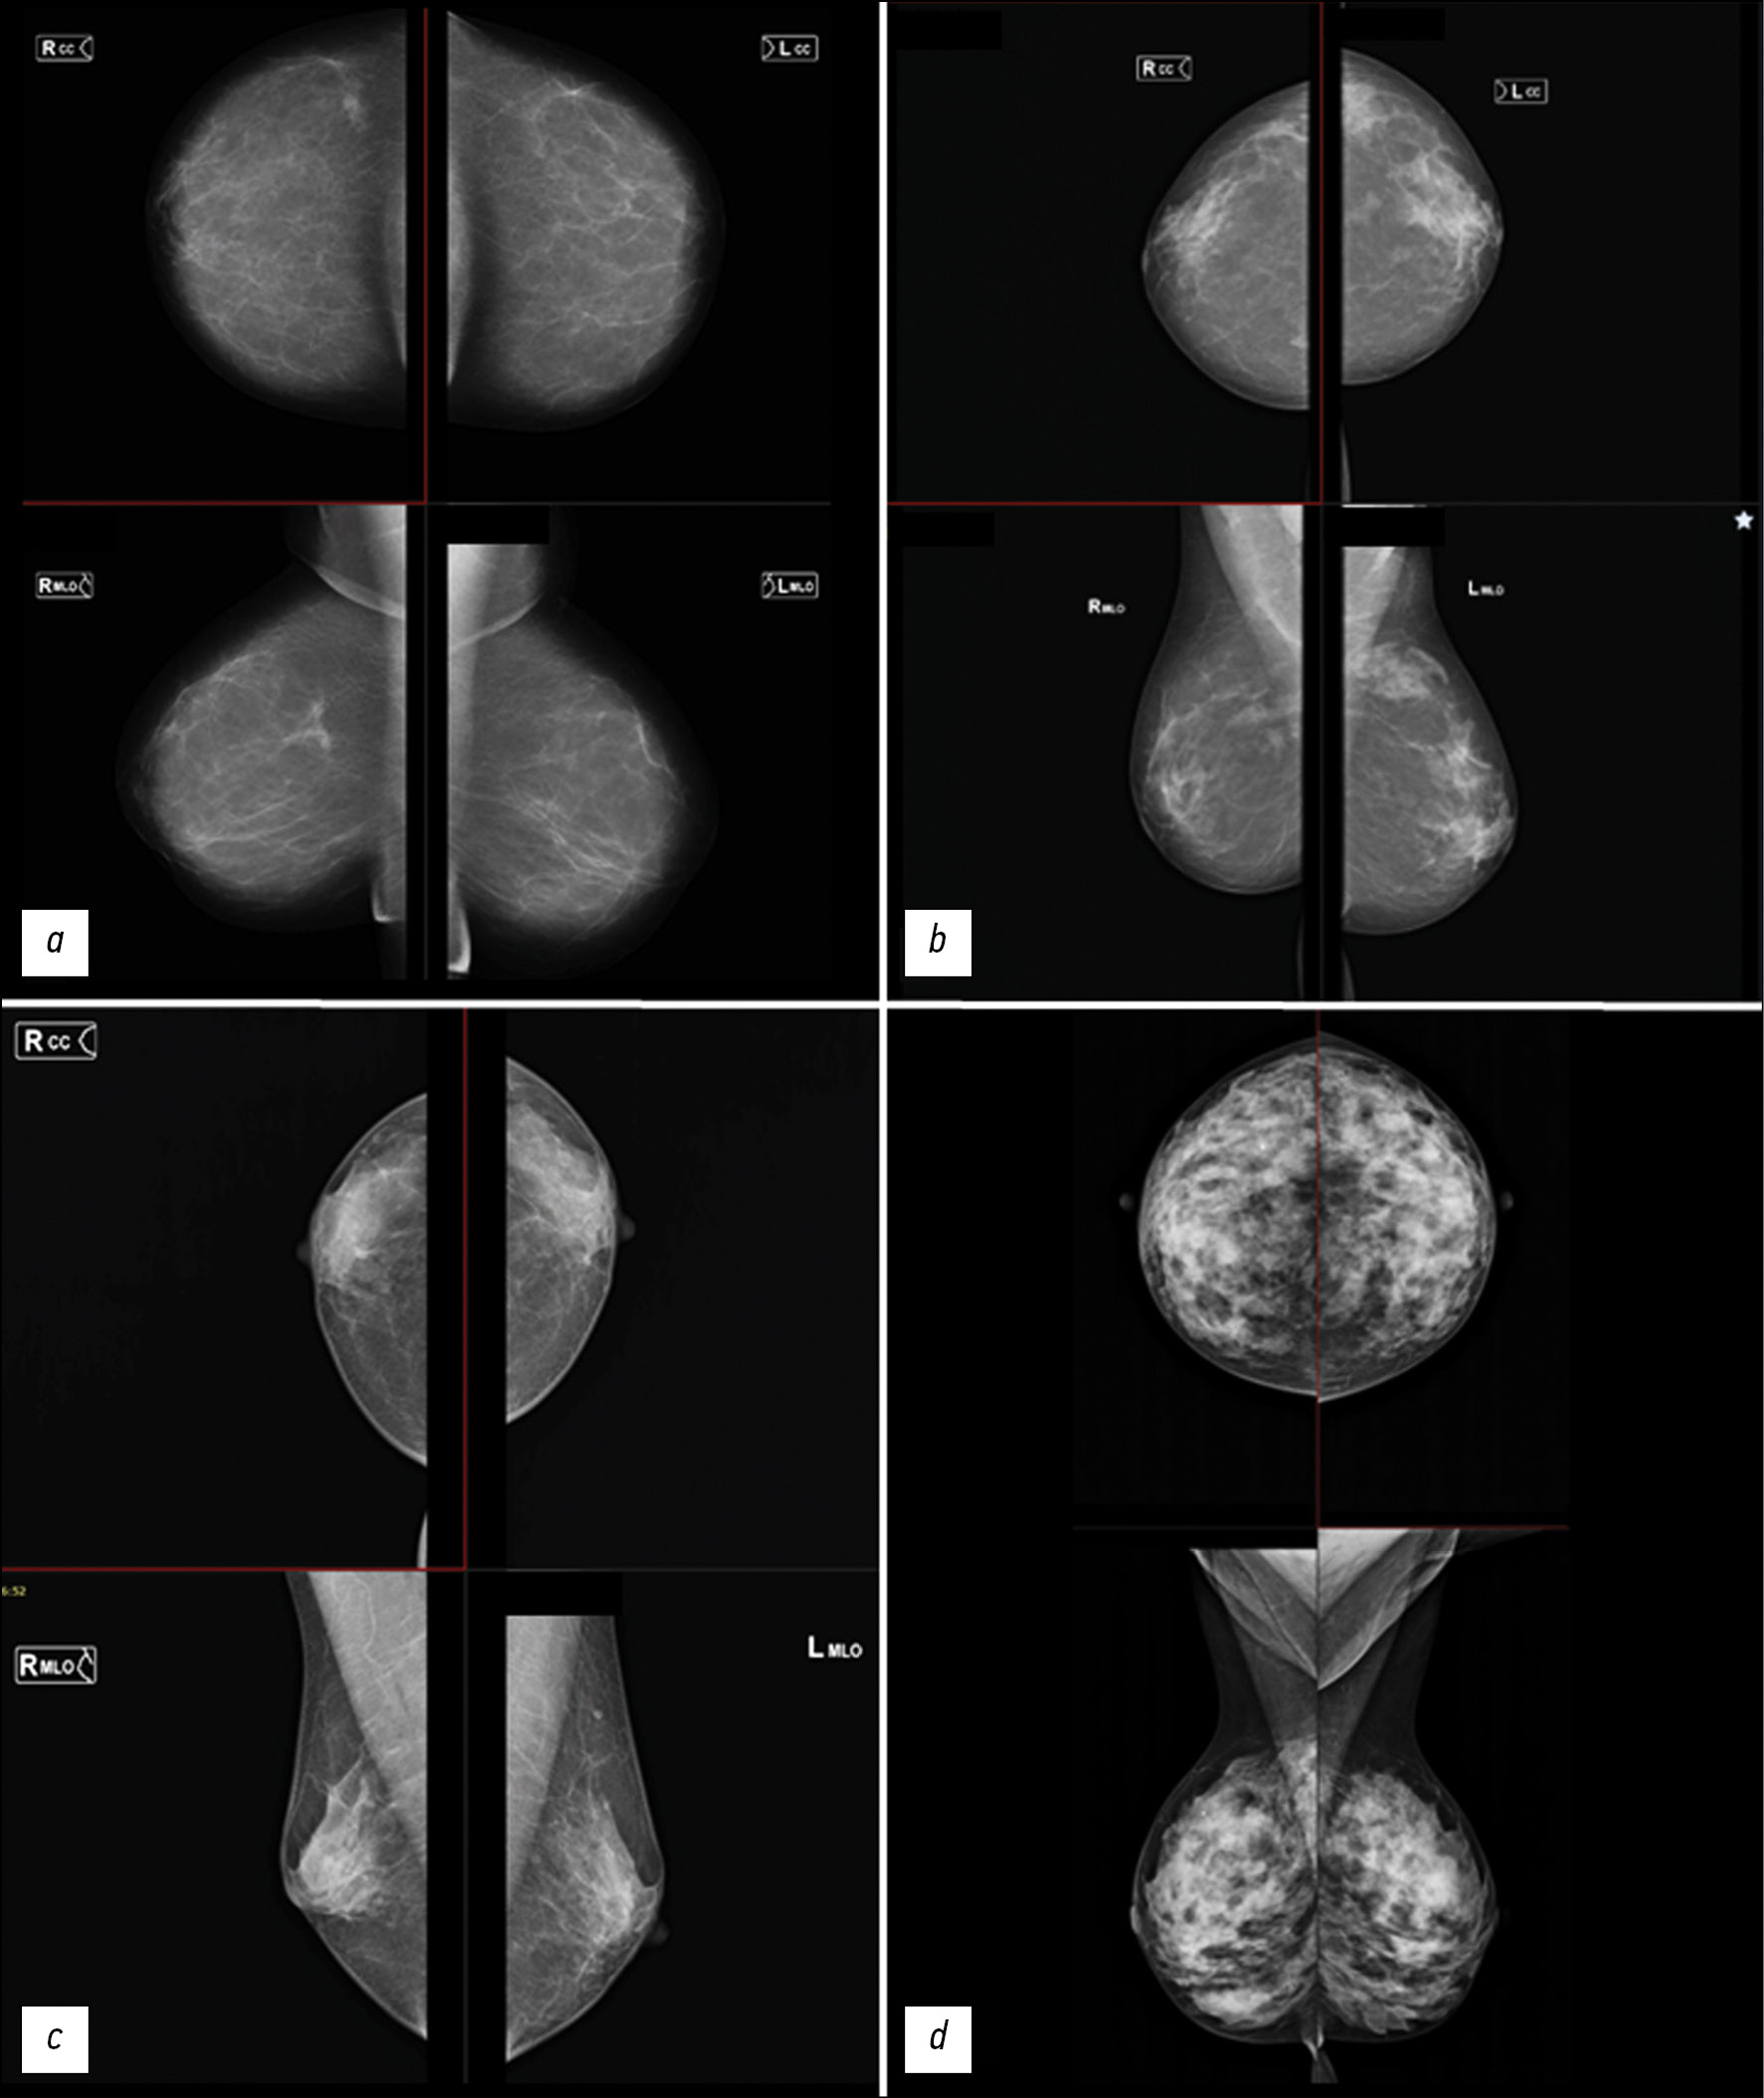

Фантомы молочной железы применяются для разработки, валидации и усовершенствования методов лучевой диагностики. В визуализации молочной железы антропоморфные модели используются для валидации, оценки и оптимизации новых методов диагностики заболеваний молочной железы, а также для контроля качества диагностических систем, совершенствования клинических протоколов и алгоритмов реконструкции изображений. Ключевым требованием к фантомам для решения этих задач является реалистичная имитация органа.

Все виды фантомов молочной железы можно разделить на два вида: вычислительные и физические. Вычислительные, в свою очередь, подразделяются на группы в зависимости от типа первичных данных: на основе математических моделей, из образцов тканей, с использований изображений медицинской визуализации молочной железы пациентки. Физические фантомы классифицируются в зависимости от способа изготовления: литья, 3D-печати или послойного формирования с использованием контрастных веществ. Основными преимуществами вычислительных фантомов являются универсальность, эффективность, точность и безопасность, а также возможность генерировать большие объёмы виртуальных данных. Физические фантомы позволяют получать наиболее реалистичные диагностические изображения без участия пациентов и проводить неограниченное число лучевых исследований.